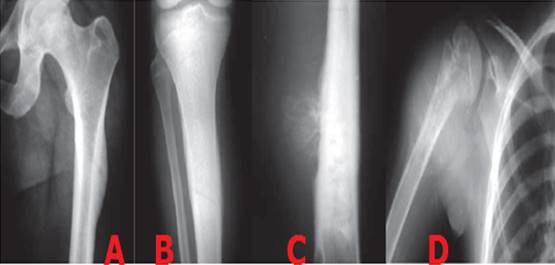

Entre los tumores óseos benignos en edad pediátrica el osteocondroma es el más frecuente, 8,9) el cual fue descrito por primera vez en el año 1818 por Astley Cooper, citado por Kumar M et al. 10 mientras que en los malignos los más frecuentes son el tumor de Ewing, 11,12) y el osteosarcoma o sarcoma osteogénico. 13,14

La edad es el factor más importante para hacer un diagnóstico diferencial cuando un radiólogo se enfrenta a una lesión ósea. 19) Los tumores óseos pueden aparecer a cualquier edad pero cada tipo histológico tiene una franja de edad de presentación característica, por ejemplo el quiste óseo solitario o esencial aparece entre los 10 a 15 años, 20 el Ewing entre ocho y 16 años, 12 el osteosarcoma de 10 a 25 años. (14 Los tumores típicos de la edad pediátrica no son exclusivos de la misma, sino que la mayoría suelen darse en adultos jóvenes también.

Los tumores primitivos malignos del hueso son poco frecuentes y en general de evolución muy rápida, los más habituales son el sarcoma de Ewing y el osteosarcoma, 35 en su tratamiento se combina la quimioterapia pre y post operatoria, la radioterapia y cirugía conservadora y posterior cirugía radical). (36